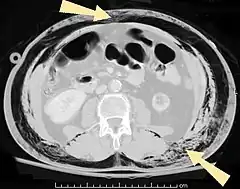

| An abdominal CT scan of a patient with subcutaneous emphysema (arrows) | |

Significant cases of subcutaneous emphysema are easy to diagnose because of the characteristic signs of the condition.[1] In some cases, the signs are subtle, making diagnosis more difficult.[13] Medical imaging is used to diagnose the condition or confirm a diagnosis made using clinical signs. On a chest radiograph, subcutaneous emphysema may be seen as radiolucent striations in the pattern expected from the pectoralis major muscle group. Air in the subcutaneous tissues may interfere with radiography of the chest, potentially obscuring serious conditions such as pneumothorax.[18] It can also reduce the effectiveness of chest ultrasound.[27] On the other hand, since subcutaneous emphysema may become apparent in chest X-rays before a pneumothorax does, its presence may be used to infer that of the latter injury.[13] Subcutaneous emphysema can also be seen in CT scans, with the air pockets appearing as dark areas. CT scanning is so sensitive that it commonly makes it possible to find the exact spot from which air is entering the soft tissues.[13] In 1944, M.T. Macklin and C.C. Macklin published further insights into the pathophysiology of spontaneous Macklin's Syndrome occurring as a result of a severe asthmatic attack.